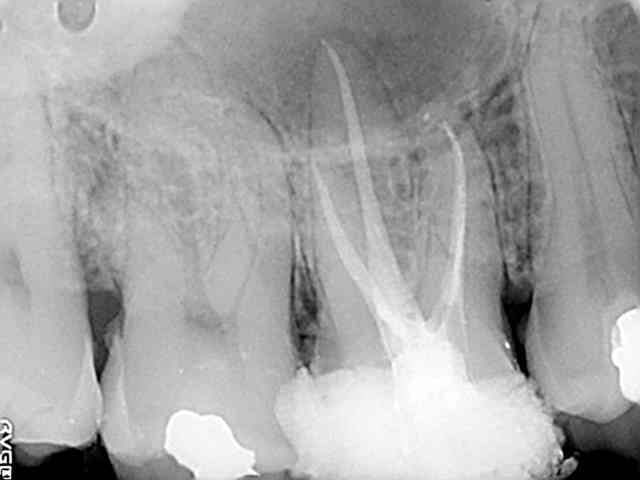

Après avoir reçu son devis, il a disparu dans la nature, et aujourd'hui, il revient la bouche en coeur avec ça.

En tout cas t'as pas tout perdu, tu as une jolie photo pour montrer aux autres patients les conséquences de "faites juste les soins on verra pour la couronne après".

Je peux t'emprunter ta photo pour faire peur à mes patients s'ils ne couronnent pas leurs dents ?? Elle est éloquente.

Oui, oui, tu peux l'emprunter.

Pour ce patient, je pense qu'il est vraiment dans un autre monde. Je lui ai annoncé que sa dent était à extraire cela ne lui a fait ni chaud ni froid. Il ne m'a même pas sorti la phrase habituelle "bah c'est pas grave, après on mettra une couronne", non, ça doit être un de ceux qui s'en fichent tant que ça ne leur fait pas mal et que ça ne leur coûte rien.